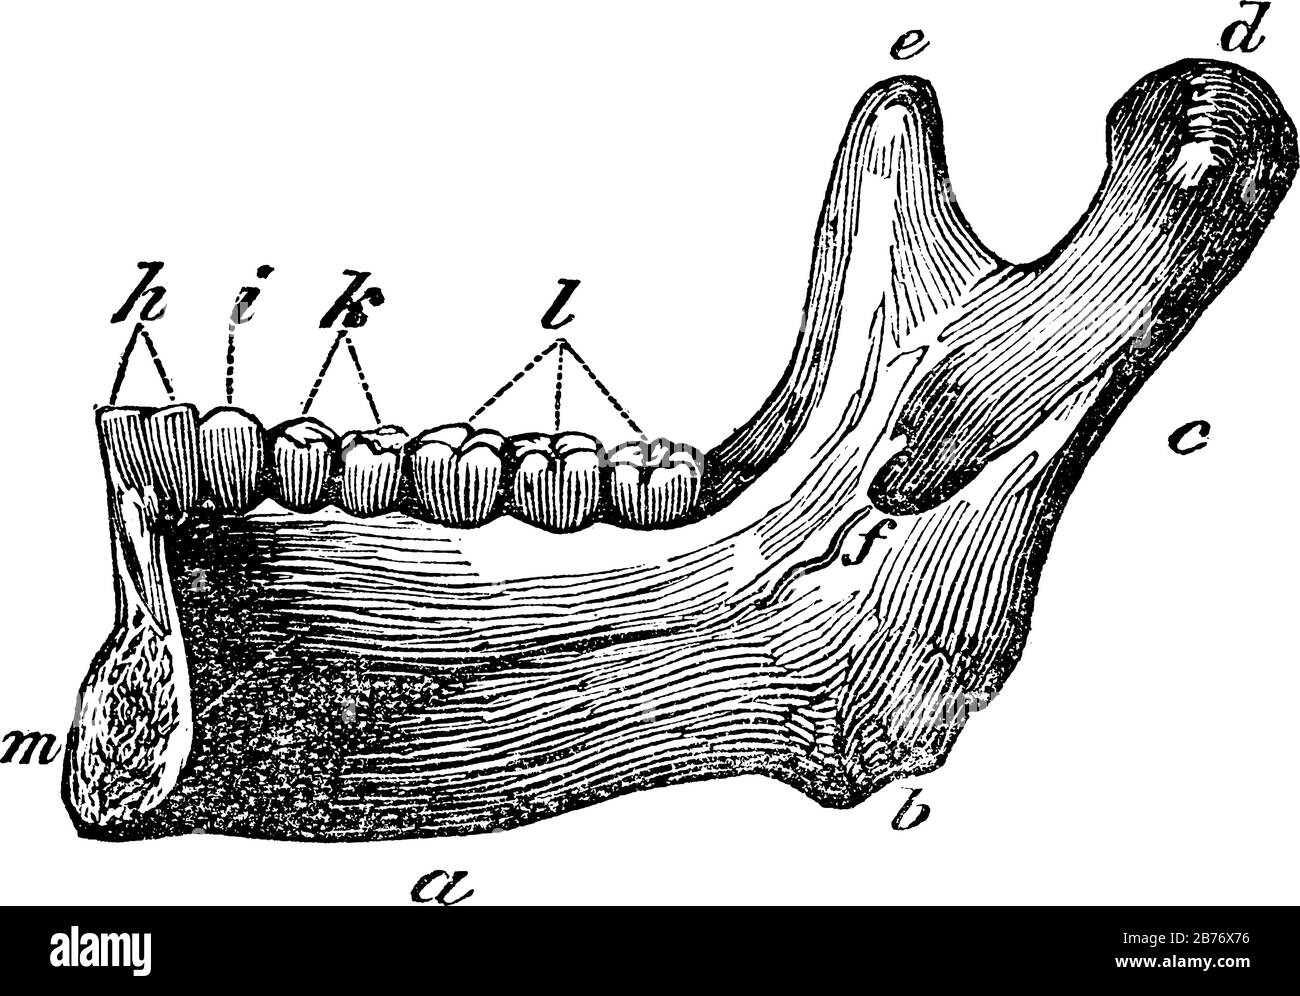

Moitié de la mâchoire inférieure. Étiquettes: A, la base; b, l'angle; c, le ramus; d, le condyle; e, le processus coronaid; h, les deux incisives; et autre, vinta Illustration de Vecteurhttps://www.alamyimages.fr/image-license-details/?v=1https://www.alamyimages.fr/moitie-de-la-machoire-inferieure-etiquettes-a-la-base-b-l-angle-c-le-ramus-d-le-condyle-e-le-processus-coronaid-h-les-deux-incisives-et-autre-vinta-image348662250.html

Moitié de la mâchoire inférieure. Étiquettes: A, la base; b, l'angle; c, le ramus; d, le condyle; e, le processus coronaid; h, les deux incisives; et autre, vinta Illustration de Vecteurhttps://www.alamyimages.fr/image-license-details/?v=1https://www.alamyimages.fr/moitie-de-la-machoire-inferieure-etiquettes-a-la-base-b-l-angle-c-le-ramus-d-le-condyle-e-le-processus-coronaid-h-les-deux-incisives-et-autre-vinta-image348662250.htmlRF2B76X76–Moitié de la mâchoire inférieure. Étiquettes: A, la base; b, l'angle; c, le ramus; d, le condyle; e, le processus coronaid; h, les deux incisives; et autre, vinta